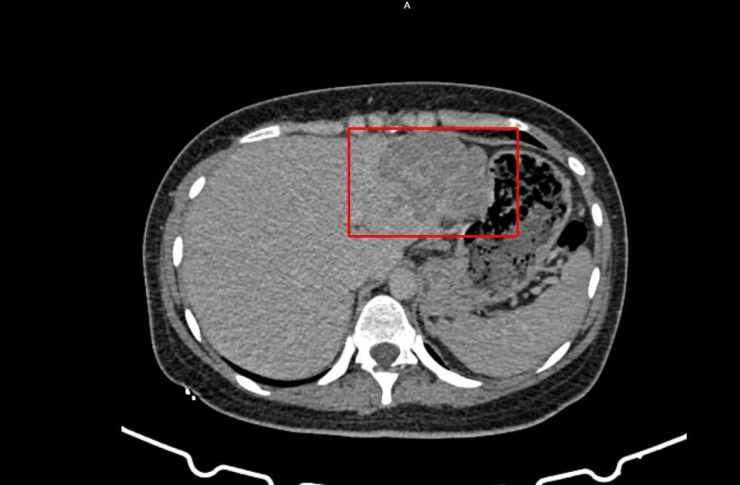

Vùng gan bị tổn thương trên hình ảnh kiểm tra được các bác sĩ ghi nhận

Kết quả cho thấy bệnh nhân bị viêm gan siêu vi B, đồng thời chỉ số AFP (dấu ấn quan trọng trong tầm soát ung thư gan) tăng cao. Hình ảnh CT-Scan bụng có cản quang cũng ghi nhận tổn thương phù hợp với u gan, ung thư biểu mô tế bào gan.